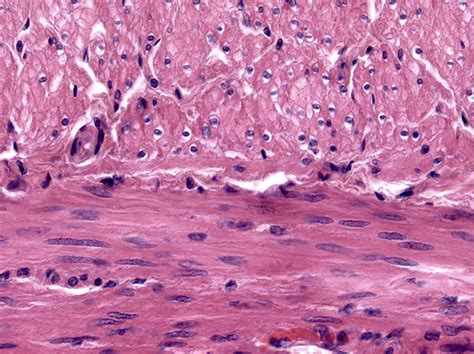

Observing Smooth Muscle Cells Under a Microscope

Once the samples are prepared, they can be observed under the appropriate microscope. Here are some key observations to look for:

• Cell Shape: Smooth muscle cells appear spindle-shaped with tapered ends.

• Nucleus: The nucleus is centrally located and appears oval or elongated.

• Cytoplasm: The cytoplasm contains actin and myosin filaments, which are responsible for contraction.

• Organelles: Various organelles, such as mitochondria and endoplasmic reticulum, are visible and play roles in cellular metabolism and protein synthesis.